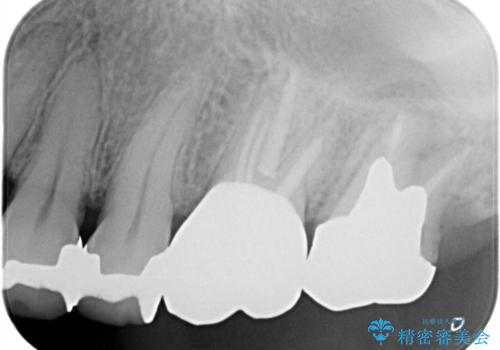

【再根管治療】オールセラミッククラウンによる修復

- 治療途中の歯があることを主訴に来院されました。

根管治療を行なったのちオールセラミックにて修復治療を行なっております。

第二大臼歯の治療は希望されませんでした。